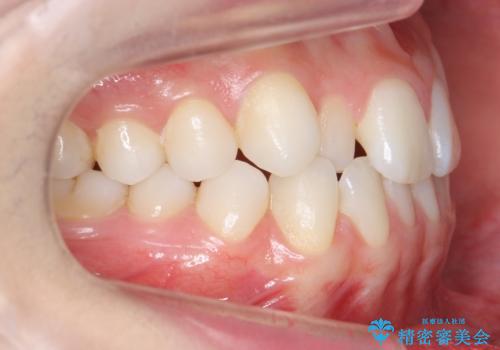

前から2番目の歯が小さく、細くとがった形になっていました。

大きくしようにも、幅が少ない上に、また、内側に入ってしまっているため、矯正治療で前歯を並べてからセラミックでかぶせることにしました。

いきなりセラミックでかぶせるよりも手間をかけた分、自然な仕上がりになっています。

先に矯正治療をすることで、下の前歯を内側に入れることができ、上の歯のセラミックの幅や厚みを取ることができました。